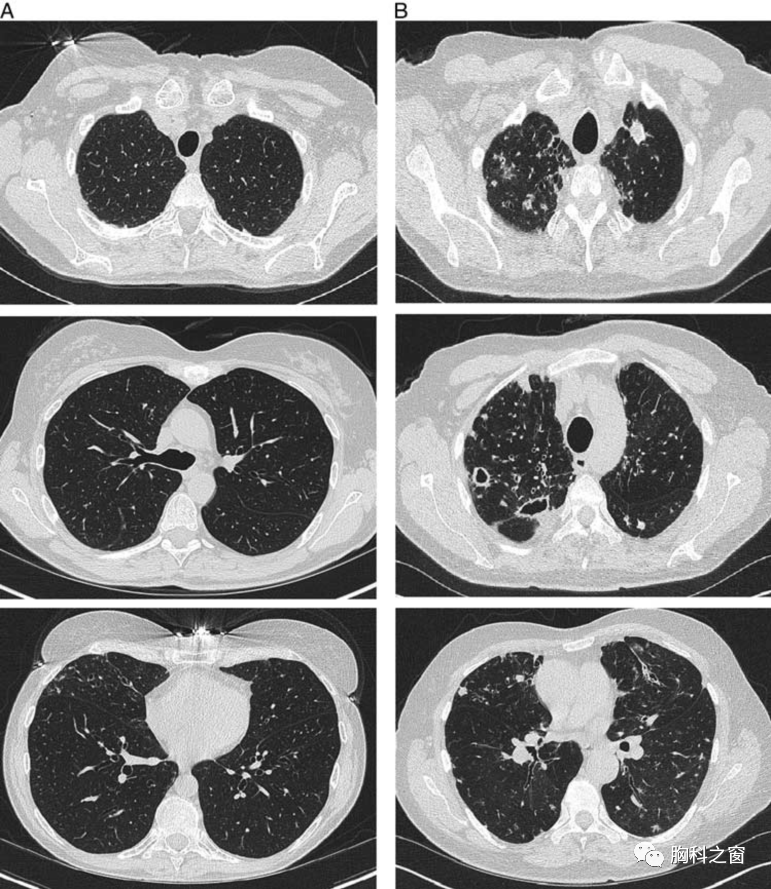

非结核性肺分枝杆菌病与无症状定植胸部ct特征:一项横断面队列研究

图片尺寸771x889